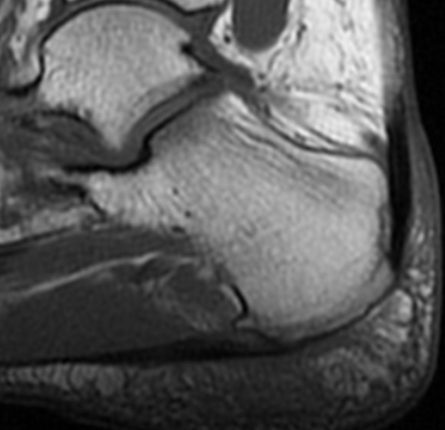

Resonancia Magnética:

- Engrosamiento focal y alteración de señal en la inserción del tendón de aquiles al calcáneo.

- Bursitis retrocalcánea y rotroaquílea.

- Edema de médula ósea en la tuberosidad calcánea.